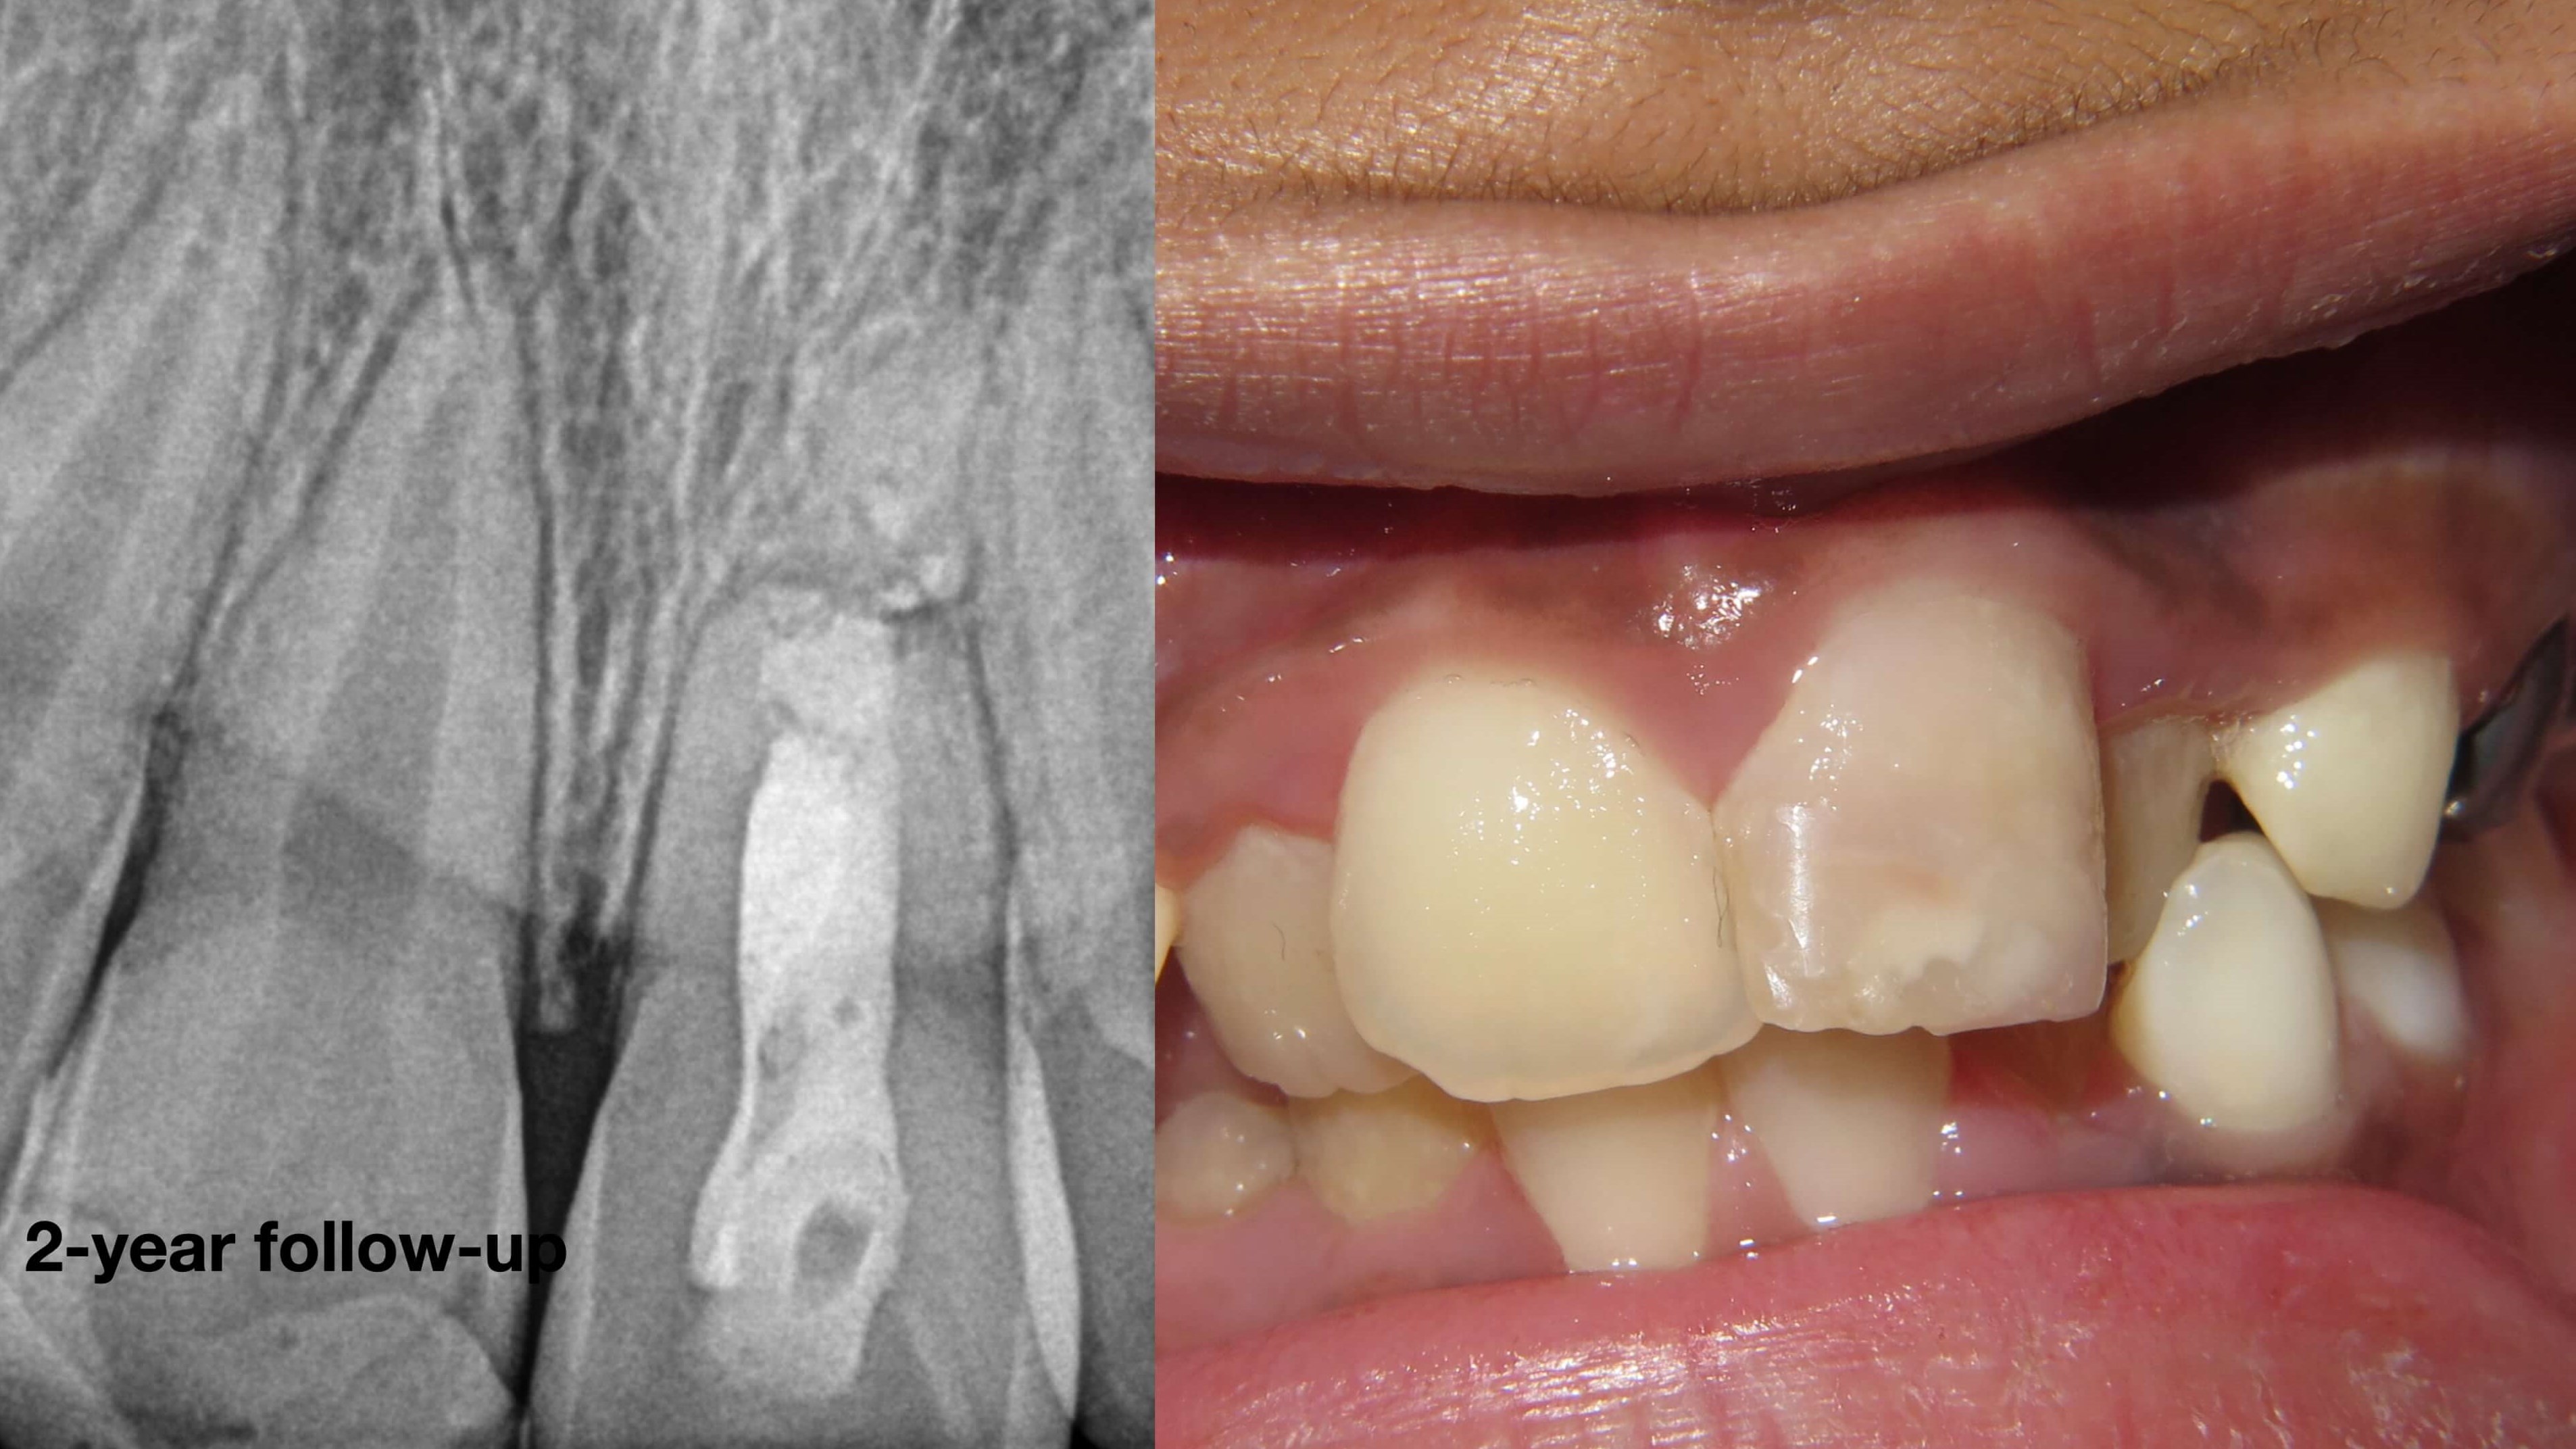

2-year follow-up after apexification with MTA as an apical plug.